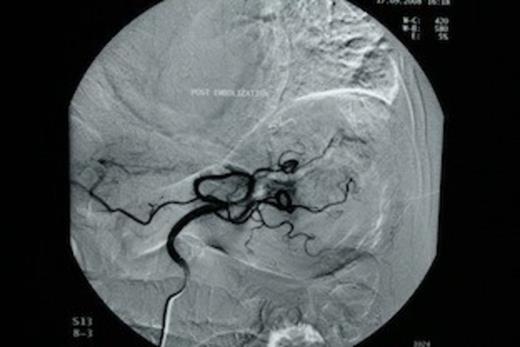

The patient was subjected to emergency oesophago-gastroduodenoscopy, which revealed extensive angiodysplasia of the gastric body. At first, conservative management was attempted with intravenous fluids and transfusions. After initial stabilization of the patient (Ht: 32.5%, 90bpm, 110/50mmHg), rebleeding was encountered within 48 hours and therefore decision for interventional radiology, embolization of the angiodysplasia, was made. Urgent angiography of the left gastric artery revealed extravasation of contrast material from the gastric body (Figure 1). Following that, successful arterial coil embolization, using super selective catheterization was achieved in the distal and proximal parts of the ruptured vessel (Figure 2). Consequently the patient recovered from the hemorrhagic shock.

Successful arterial coil embolization, using super selective catheterization in the distal and proximal parts of the ruptured vessel